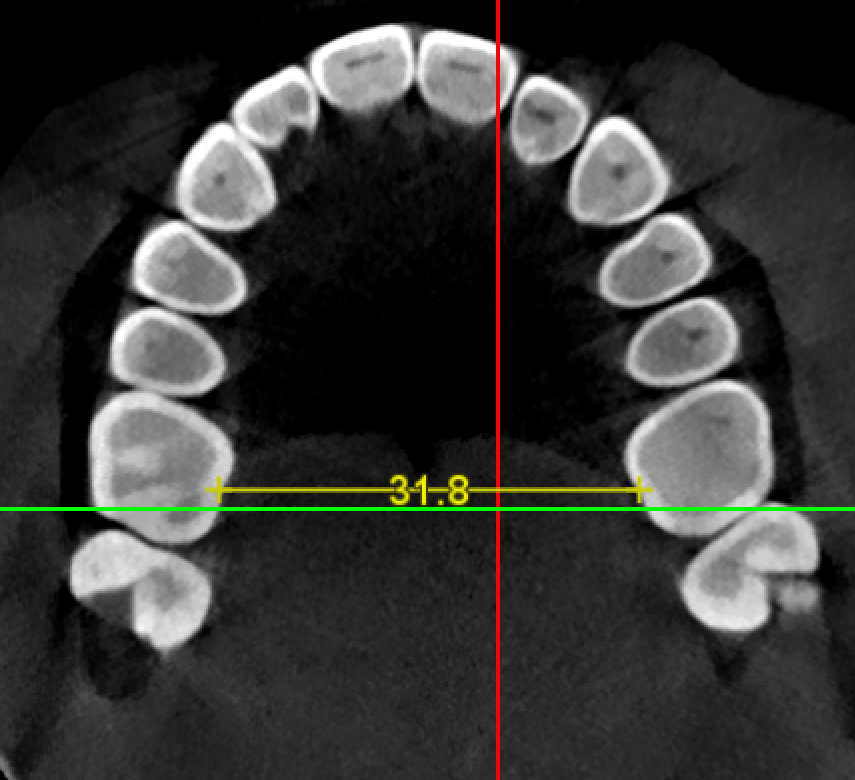

Btw the scissor method I mentioned above is super inaccurate. I just measured my width on my CT.

1661311655542

31.8mm :fuk:.